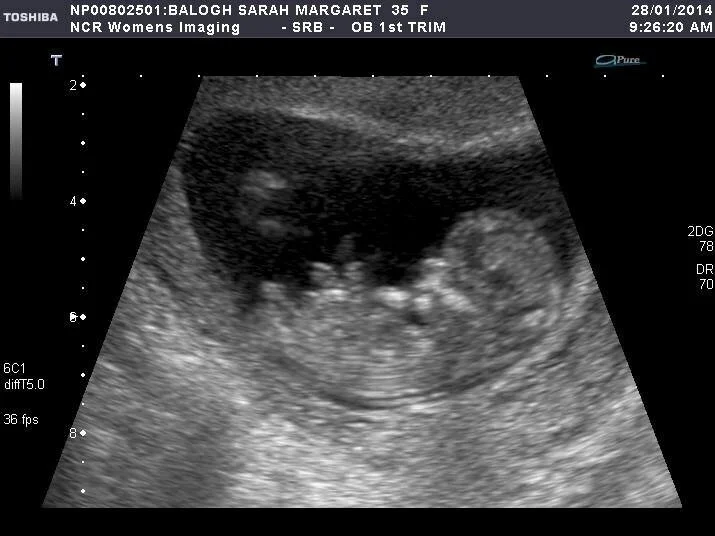

Ultrasound picture of my son Xavier at 12 weeks